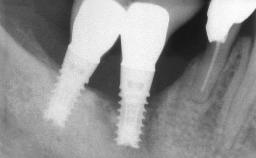

The fracture of an implant after it has been restored is one of the most severe complications. It most frequently occurs in partially edentulous jaws (1.5%). Most implant fractures involve implants with a diameter of 3.75 mm made of commercially pure titanium (Eckert 2010). Unfortunately, many cases are not reported or documented by the clinicians involved in resolving the problems created by the fracture. This case report describes the management of an implant fracture at site 36 in a middle-aged male patient. The implant had been restored with a screw-retained metal-ceramic crown.

Type of Implants Two-Piece

Retention Screw-retained Screw-retained